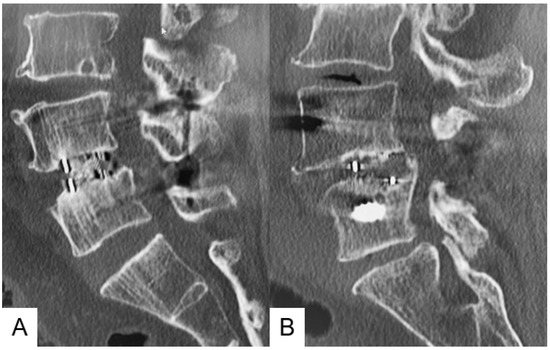

2.1. Surgical Settings and Procedures for Single-Position OLIF

2.2. Surgical Settings and Procedures for MI-PLIF/TLIF